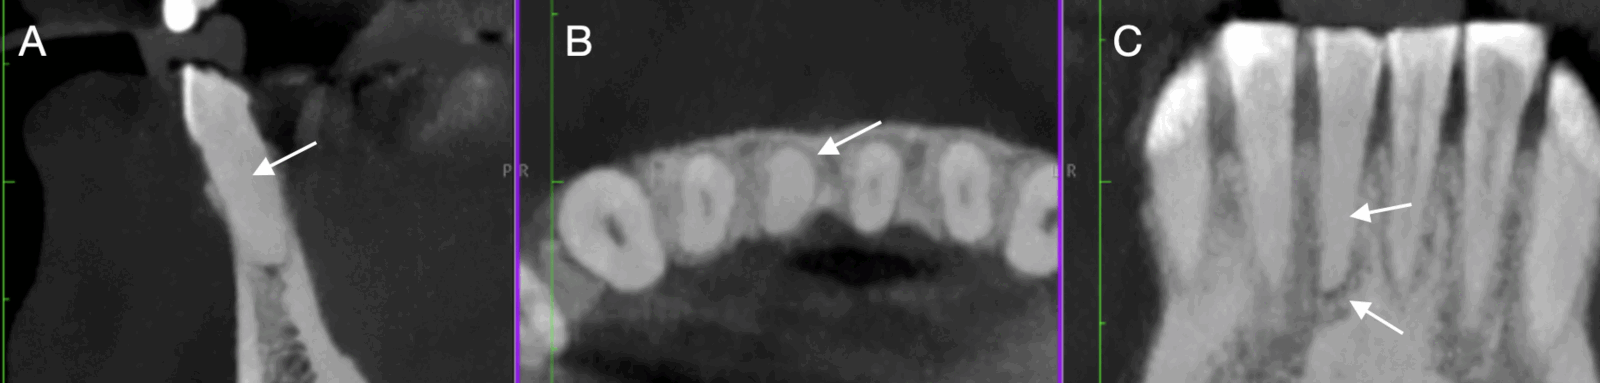

El incisivo central mandibular mostró una respuesta positiva tanto a las pruebas de percusión vertical como a las de percusión horizontal, y ninguna respuesta a la prueba de vitalidad pulpar térmica. La radiografía periapical inicial (figura 1A) demostró la presencia de obliteración severa del conducto radicular a nivel de la pulpa cameral y radicular, en comparación con los incisivos central y lateral adyacentes. El diente 41 presentaba evidencia radiográfica de periodontitis apical. Se realizó una TCHC de maxilares con un FOV 16×18 cm en un tomógrafo (GIANO HR, NewTom®, Imola, Italia). Las imágenes tomográficas confirmaron la presencia de una calcificación severa del conducto y patología periapical (figura 2).

Figura 2. Observación de obliteración severa y patología periapical en TCHC: A) Observación de obliteración severa en el corte sagital; B) Observación de obliteración severa en el corte axial; C) Observación de obliteración severa en el corte transaxial y presencia de patología periapical.